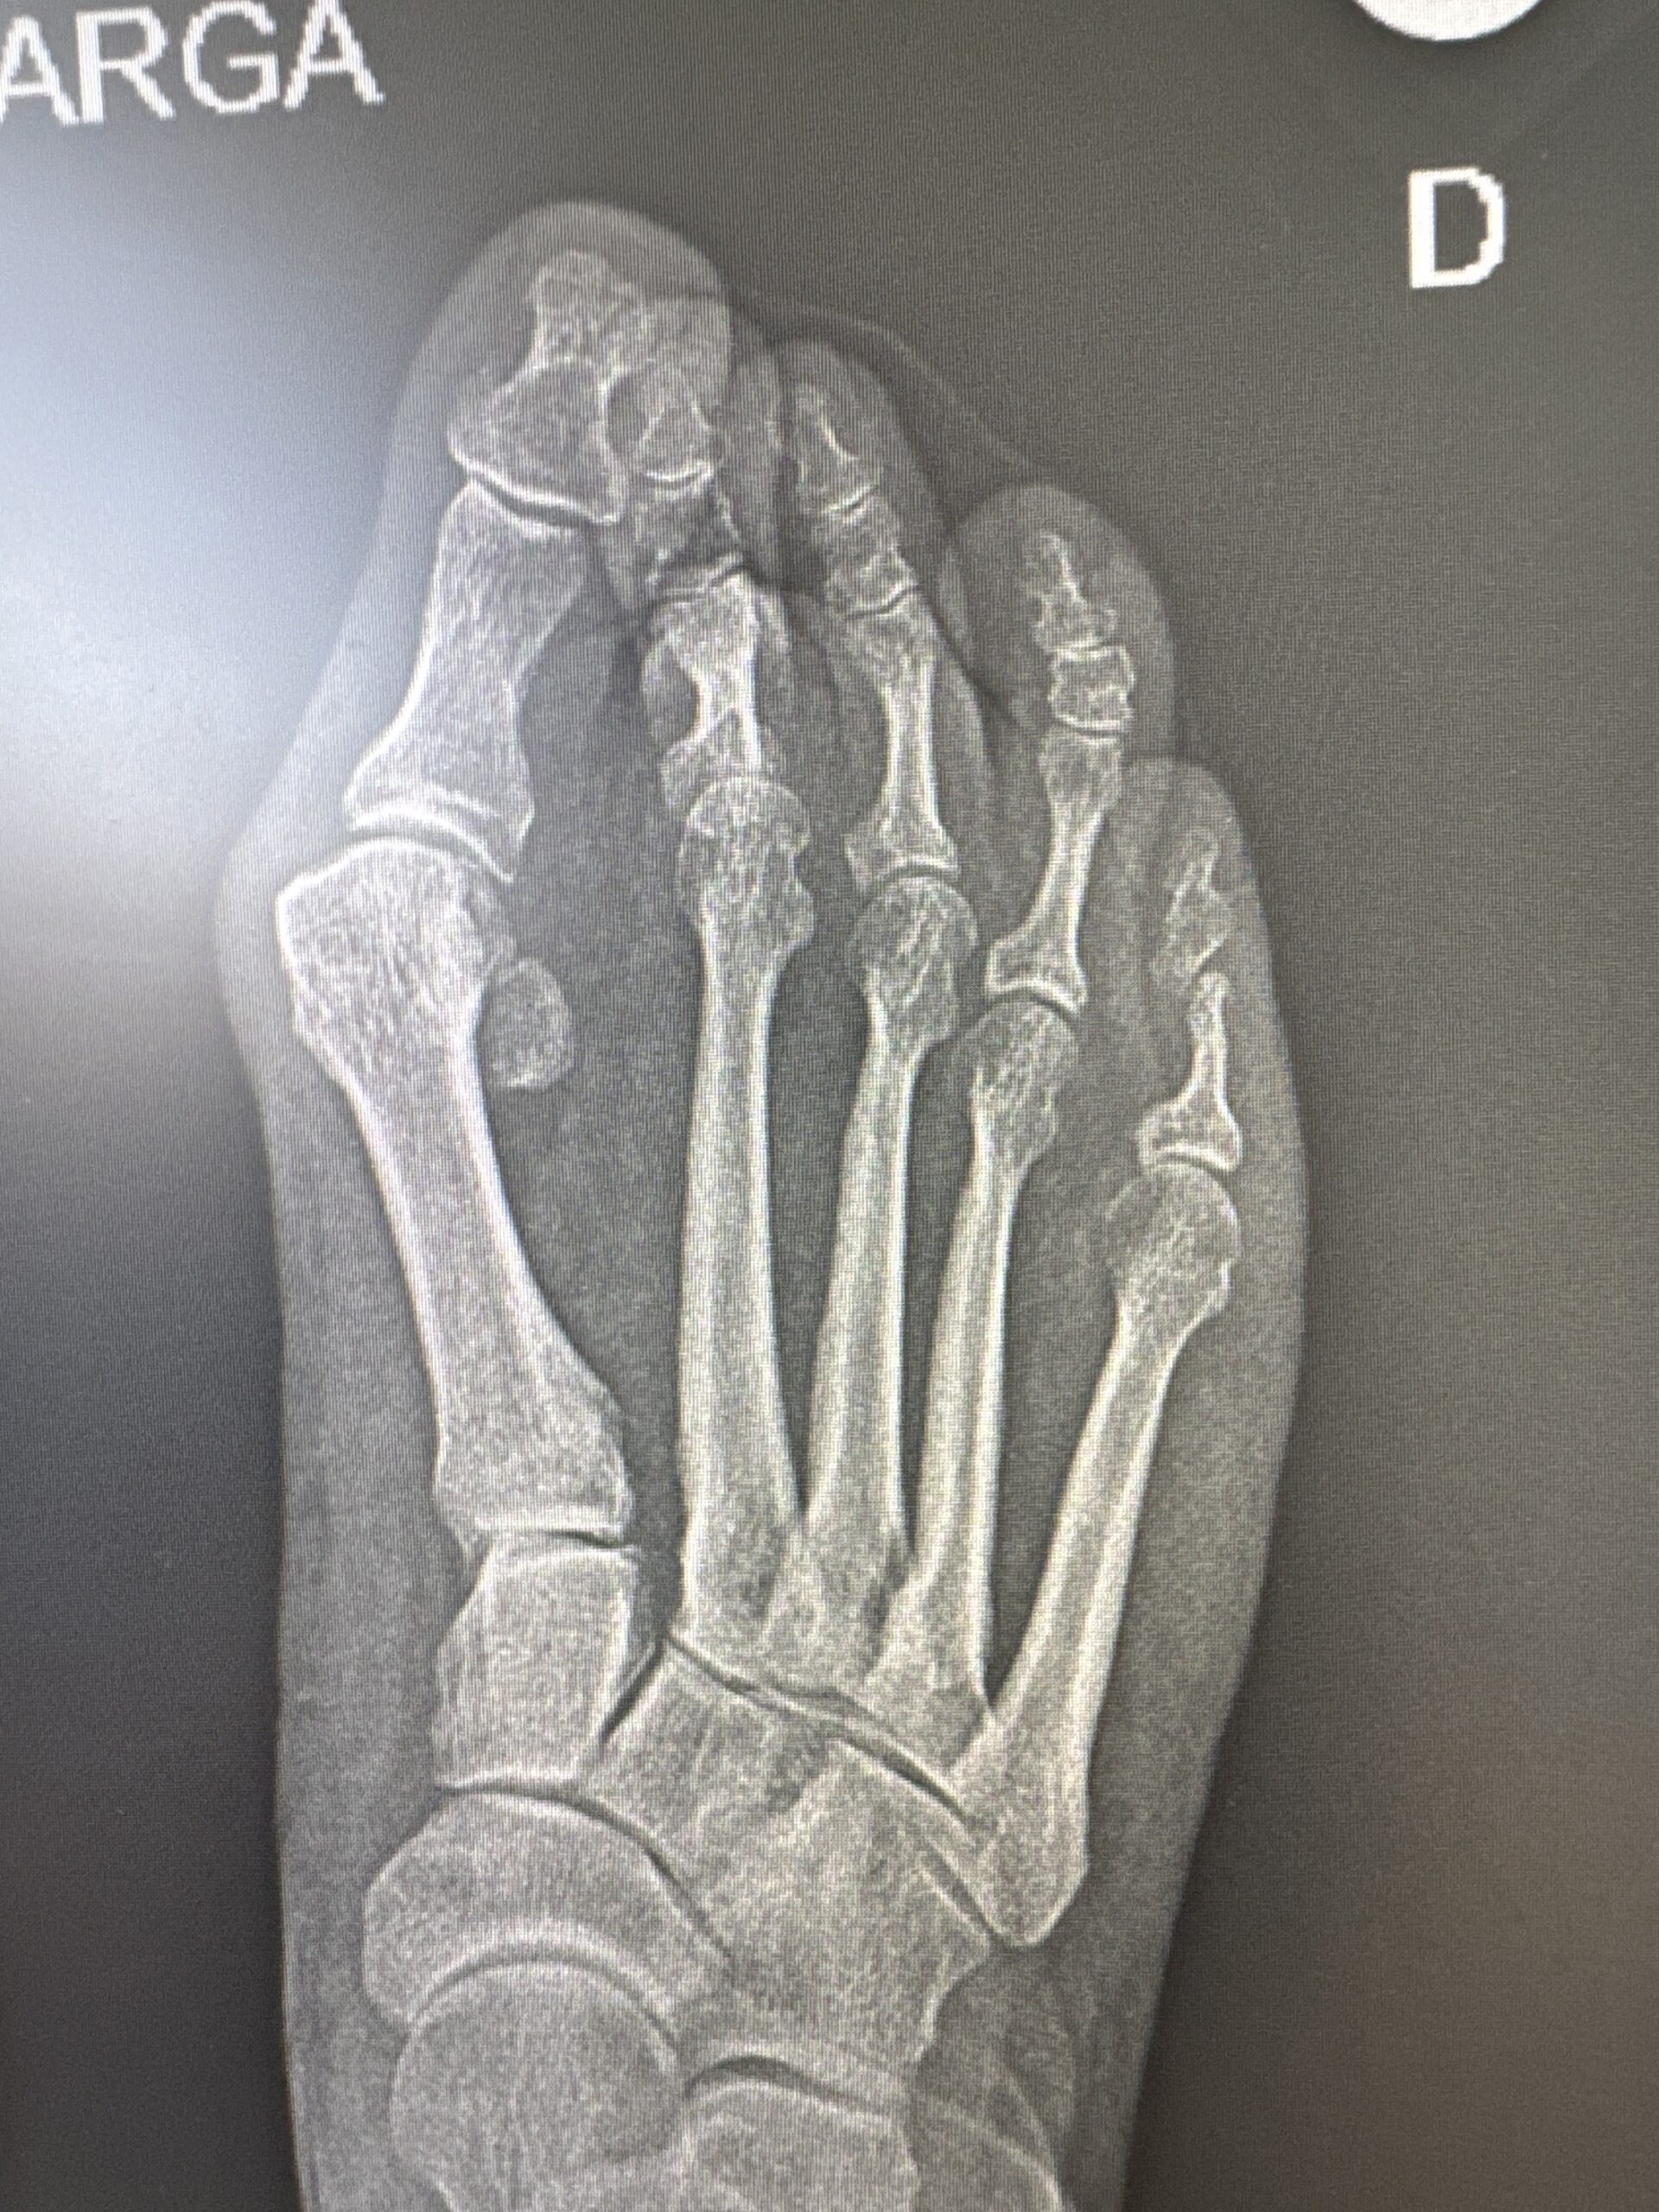

Os presento un caso de deformidad de hallux valgus intervenido con una técnica de cirugía percutánea de 3ª generación. En este ocasión, se ha realizado unas osteotomías en el primer metatarsiano y en la primera falange que se han fijado con tornillos que confiere a la corrección estabilidad, seguridad y menor dolor postoperatorio manteniendo el respeto a las partes blandas.

Los resultados radiográficos y clínicos los podéis ver en las fotos antes de la cirugía y los 3 meses de la misma.